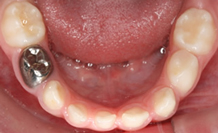

Root canal treatment for primary (Milk) teeth & early permanent

teeth

Composite fillings